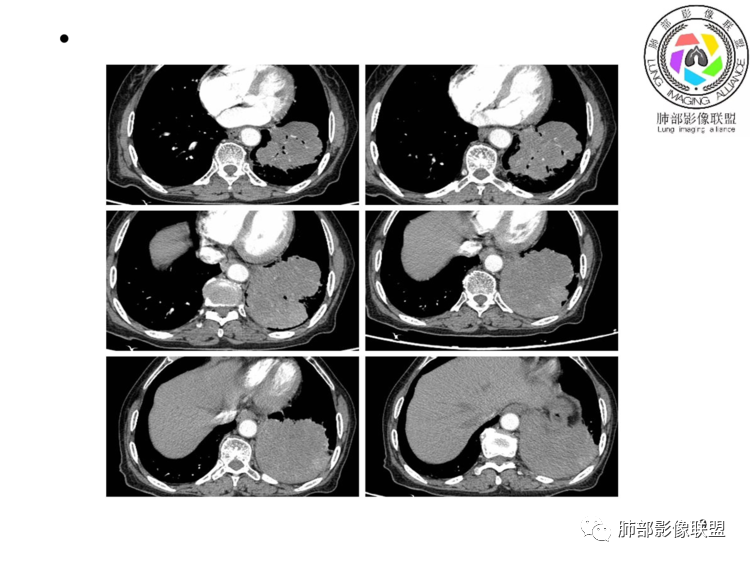

团片,内有支气管扩张,血管飘浮,不均匀强化,累膈肌似侵及脾脏,考虑恶性,淋巴瘤?肉瘤?

左肺下叶团块,边缘膨隆分叶,支气管部分阻塞、部分进入扩张,密度不均,延迟强化,血管走行正常,病灶与左侧膈肌分界不清。考虑恶性肿瘤:1淋巴瘤;2肉瘤样癌。

左肺下叶巨大实性肿块,支气管进入后阻塞,血管走行自然,增强中度均匀强化,无明显坏死。与膈肌分界不清,是否有侵犯导致腹痛症状?

考虑恶性肿瘤,低分化腺癌或者淋巴瘤?

老年女性,上腹部疼痛为主诉,CT所示左肺下叶肿块,左肺下叶支气管变窄,局部阻塞,病灶可见分叶,内见僵硬稍扩张的支气管,增强扫描病灶中度强化,内见血管造影征,首先考虑恶性病变,腺癌和淋巴瘤需要考虑,转移瘤待排除。

老年女性,以上腹痛就诊,左肺下叶团块影,边界清,可见分叶,延迟强化,内未见明显坏死,可见支气管充气扩张,血管走形自然,考虑淋巴瘤

老年女性,上腹痛就诊,CT可见左肺下叶巨大肿块,支气管进入后变窄堵塞,血管走行自然,内可见稍扩张支气管,增强均匀强化,与膈肌分界不清,考虑为恶性,淋巴瘤或腺癌可能

老年女性,左肺下叶软组织肿块,密度较均匀,边缘膨隆分叶,临近支气管截断,肿块内可见支气管穿行,与膈肌分界不清,增强后动脉期轻度均匀强化,静脉期呈渐进性强化,欠均匀,内血管走形如常,可见血管漂浮,整体感觉病灶偏软,考虑淋巴瘤可能大,鉴别腺癌。

患者老年女性,上腹部疼痛一周,无呼吸道症状,查体无阳性体征。血常规、尿常规、肝肾功能正常。肿瘤标志物CA125稍升高。胸部CT:左肺下叶肿块灶,边缘欠光滑,边界欠清楚,见分叶、血管集束征象,内见支气管扩张,增强中度强化,见血管漂浮征象。综合考虑恶性病变,淋巴瘤可能大,鉴别肺癌。

左下肺不规则巨大肿块,下叶支气管部分阻塞,部分扩张,与左侧膈肌分界不清,增强延迟强化,可见血管造影征,考虑恶性,淋巴瘤可能大,鉴别腺癌

老年女性,上腹部疼痛一周,肿标CA125升高。胸部CT:左肺下叶巨大肿块,分叶,密度不均,与左膈肌分界不清,内见枯枝征,部分支气管进入后截断,增强中度延迟强化,见血管漂浮征。胃壁不均匀增厚。考虑:恶性肿瘤病变伴阻塞性炎症,淋巴瘤?腺癌转移?鉴别TB、隔离等。

老年女性,左下肺大肿块、深分叶,考虑恶性肿瘤。纵隔肺门淋巴结无明显肿大,不支持小细胞癌;支气管进入后截断、肿块破坏力不强,不支持鳞癌,内部血管走行自然,不怎么支持腺癌,支持淋巴瘤;肉瘤似乎内部很少见支气管。

左肺下叶实变影,形态尚规则,外缘欠光滑,呈膨胀性生长,叶裂推移,近段支气管穿行,支气管略扩张,平扫密度均匀,增强后可见穿行血管,老年女性,无感染症状,实验室检查肿瘤标志物高,考虑恶性:1:淋巴瘤;2:腺癌;3:IMT

左下肺肿物,有分叶及血管飘浮征,定性恶性,无胸膜牵拉及毛刺,提示收缩力差,可排除腺癌。女性,肿块内坏死不明显(鳞烂心)不首选鳞癌。老年女性,血管飘浮,特别是膈肌受累首选淋巴瘤

定位,肺内,血管支气管穿行

定性,恶性,腺癌跟淋巴瘤鉴别

腺癌支持点就是常见病,发病率高,CEA高。不好解释血管穿行比较自然。病灶整体偏软,所以淋巴瘤放前面

考虑淋巴瘤!鉴别腺癌 首先看病灶恶性征象多,深分叶支气管截断,支气管感觉是受压闭塞,肺动脉显示良好,血管漂浮征!这么大肿瘤如果是鳞癌不可能没有坏死!腺鳞癌同样如此,肉瘤样癌同理,类癌、不典型类癌明显强化,而这例轻度延迟性比较均匀强化,淋巴瘤感觉是符合 特别是MALT

弥漫性大B细胞淋巴瘤